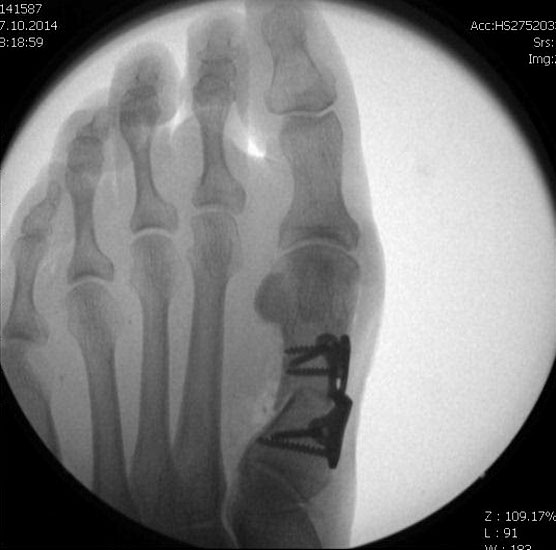

Jetzt erfolgt das Einbringen der Fräse im 45°-Winkel von distal dorsal nach proximal plantar. Auf steten Knochenkontakt mit der Kortikalis zur Vermeidung eines Weichteilinterponates sollte geachtet werden. In unserer Abteilung erfolgt vor Beginn der Osteotomie nun eine nochmalige Lagekontrolle der Fräse unter dem Bildwandler im dorsoplantaren Strahlengang. Eine zusätzliche laterale Aufnahme kann die Tiefe der eingebrachten Fräse in Bezug auf das zu osteomierende Metatarsale zeigen, ebenso ermöglicht sie eine Kontrolle des 45°-Winkels.

In einer rotatorischen Bewegung mit dem Drehpunkt im Bereich der Hautinzision erfolgt nun die Osteotomie zunächst - in Abhängigkeit von der zu operierenden Seite und der Rechts- oder Linkshändigkeit des Operateurs  - des medialen bzw. lateralen Kortex des Metatarsale, gefolgt von den plantaren Anteilen und anschliessend dem gegenseitigen Kortex. Am Ende der rotatorischen Bewegung befindet sich die Fräse, die am Anfang der Osteotomie noch parallel zum Metatarsaleschaft ausgerichtet war, im 90°-Winkel zu diesem.

Mit dem plantar unter dem Metatarsaleköpfchen aufliegenden Zeigefinger der Gegenhand kann die Vollständigkeit der  Osteotomie durch ein Nachlassen der Widerstandes unter dem Köpfchen palpiert werden. Falls nötig, kann dies auch durch Zug an der Zehe unter Bildwandler zusätzlich bestätigt werden. Das Metatarsaleköpfchen wandert durch die Osteotomie von allein um einige mm nach proximal und dorsal.  Eine zusätzliche manuelle Verkürzung des Metatarsale ist aus biomechanischen Gründen zu vermeiden.